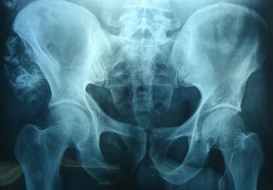

Kemikte Hangi Mineraller Bulunur ve İşlevleri Nelerdir?Kemikler, insan vücudunun temel yapısal bileşenleridir ve birçok önemli mineral içerir. Bu mineraller, kemiklerin güçlü ve sağlıklı kalmasına yardımcı olurken, aynı zamanda vücudun diğer işlevlerinde de kritik rol oynamaktadır. Bu makalede, kemikte bulunan başlıca mineraller ve bunların işlevleri detaylı bir şekilde incelenecektir. KalsiyumKalsiyum, kemiklerin ana bileşenidir ve kemiklerin gücünü ve bütünlüğünü sağlamak için kritik öneme sahiptir. Kalsiyum, kas kasılmaları, sinir iletimi ve kan pıhtılaşması gibi birçok vücut fonksiyonu için gereklidir. Vücutta yeterli kalsiyum bulunmaması durumunda, kemiklerin mineral yoğunluğu azalabilir, bu da osteoporoz gibi hastalıklara yol açabilir. FosforFosfor, kemiklerin oluşumunda ve bakımında önemli bir rol oynar. Kalsiyumla birlikte, kemiklerin mineralizasyonunu sağlar. Fosfor, enerji üretimi, hücre onarımı ve DNA sentezi gibi birçok biyolojik süreçte de yer alır. Fosfor ve kalsiyum arasındaki denge, kemik sağlığı açısından kritik öneme sahiptir. MagnesiumMagnezyum, kemiklerin yapısında bulunur ve kalsiyum ile birlikte çalışarak kemiklerin güçlü kalmasını destekler. Ayrıca, magnezyumun sinir ve kas fonksiyonları üzerinde de olumlu etkileri vardır. Magnezyum eksikliği, kemik sağlığını olumsuz etkileyebilir ve osteoporoz riskini artırabilir. FlorürFlorür, diş sağlığı ile daha çok bilinse de, kemik sağlığı üzerinde de olumlu etkileri vardır. Florür, kemiklerin mineralizasyonunu artırabilir ve osteoporoz riskini azaltabilir. Ancak, aşırı florür alımı, fluorosis adı verilen bir duruma yol açabilir ve bu da kemiklerde zayıflamaya neden olabilir. ÇinkoÇinko, kemik sağlığı için önemli bir mineraldir ve kemik oluşumunu destekler. Aynı zamanda bağışıklık sistemi fonksiyonunu güçlendirmeye yardımcı olur. Çinko eksikliği, kemiklerin zayıflamasına ve osteoporoz riskinin artmasına neden olabilir. BakırBakır, kemiklerin sağlıklı bir şekilde gelişmesine yardımcı olur ve bağ dokusu sentezinde rol oynar. Bakır eksikliği, kemik mineral yoğunluğunun azalmasına ve çeşitli kemik hastalıklarına yol açabilir. DemirDemir, hemoglobin yapısında önemli bir mineral olmasının yanı sıra, kemiklerin sağlıklı gelişimi için de gereklidir. Demir eksikliği, kemik sağlığını doğrudan etkilemese de, genel sağlık durumunu olumsuz etkileyebilir ve bu da dolaylı olarak kemiklerin sağlığını etkileyebilir. SonuçKemikler, sağlıklı bir yaşam için gerekli olan birçok minerali içermektedir. Kalsiyum, fosfor, magnezyum, florür, çinko, bakır ve demir, kemiklerin güçlenmesine ve sağlıklı kalmasına yardımcı olan önemli minerallerdir. Bu minerallerin dengeli bir şekilde alınması, kemik sağlığını korumak için kritik öneme sahiptir. Özellikle, yeterli beslenme ve düzenli fiziksel aktivite, kemik sağlığını desteklemek için önemlidir. Her bireyin mineral ihtiyaçları farklılık gösterebilir, bu nedenle bireysel beslenme planları oluşturmak faydalı olacaktır. |